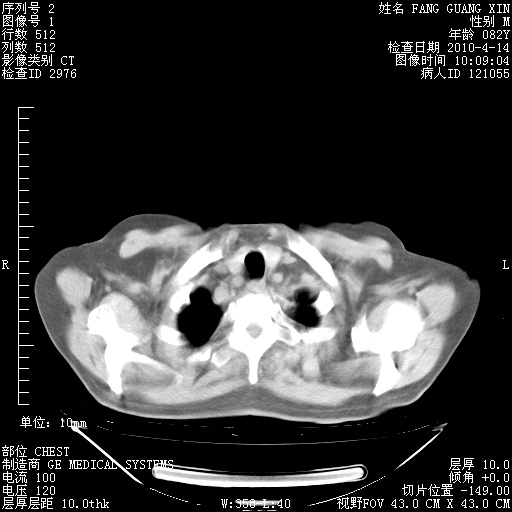

肺部CT平扫未见异常。